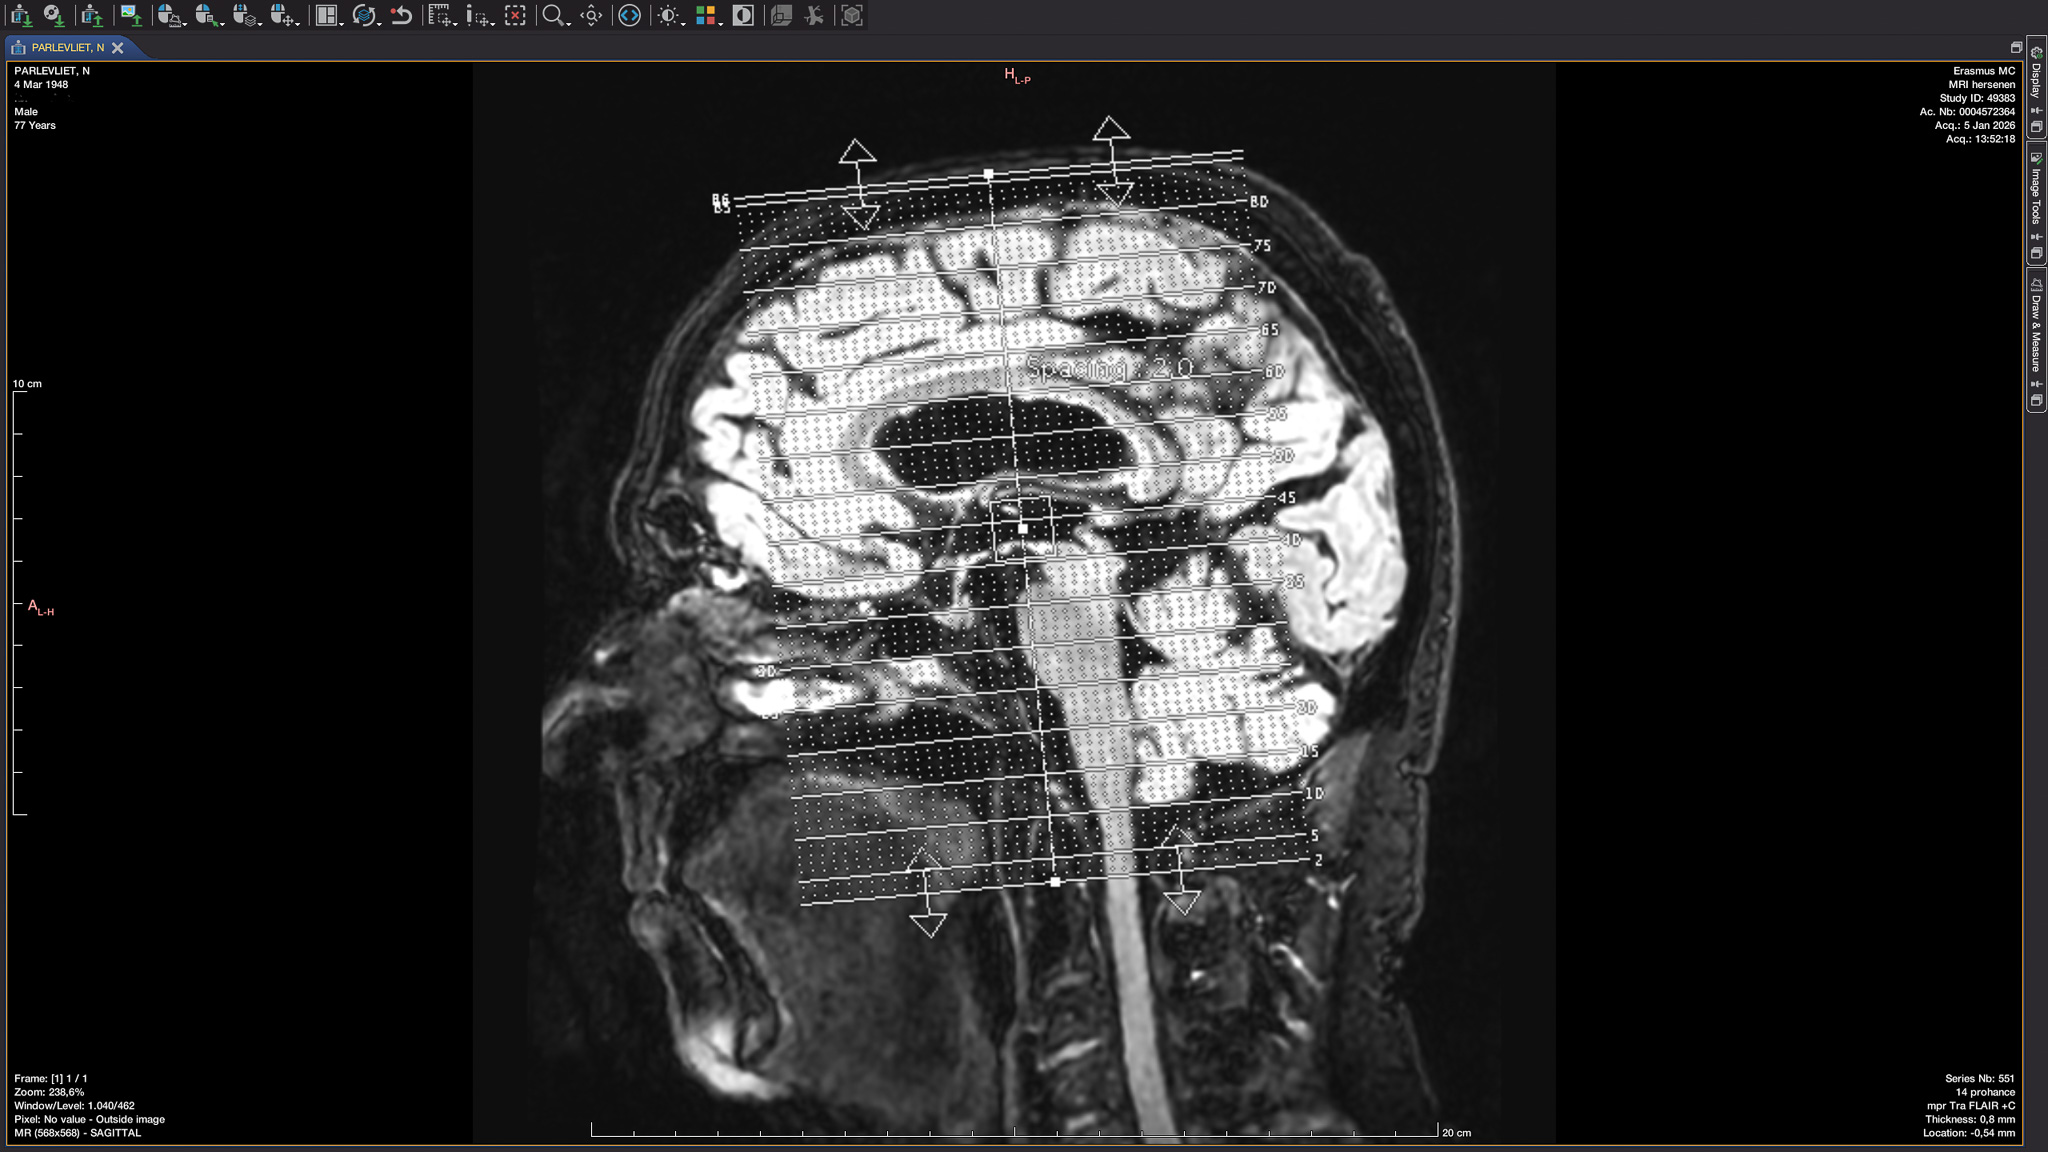

2026 – Hoofdzakelijk Stilte is een solitaire performance in mijn atelier. Voor de duur van 1 minuut heb ik links en rechts van mijn hoofd een microfoon gehouden om geluid van binnenuit te kunnen vangen. Opnamedag was de eerste dag van het jaar 2026, het jaar waarin mijn hersenen al vroeg een belangrijk onderwerp zijn geworden.

Mainly Head Silence is a solitary performance in my studio. For one minute, I held a microphone to the left and right sides of my head to capture sound from within. Recording day was the first day of 2026, the year in which my brain became an important subject early on.